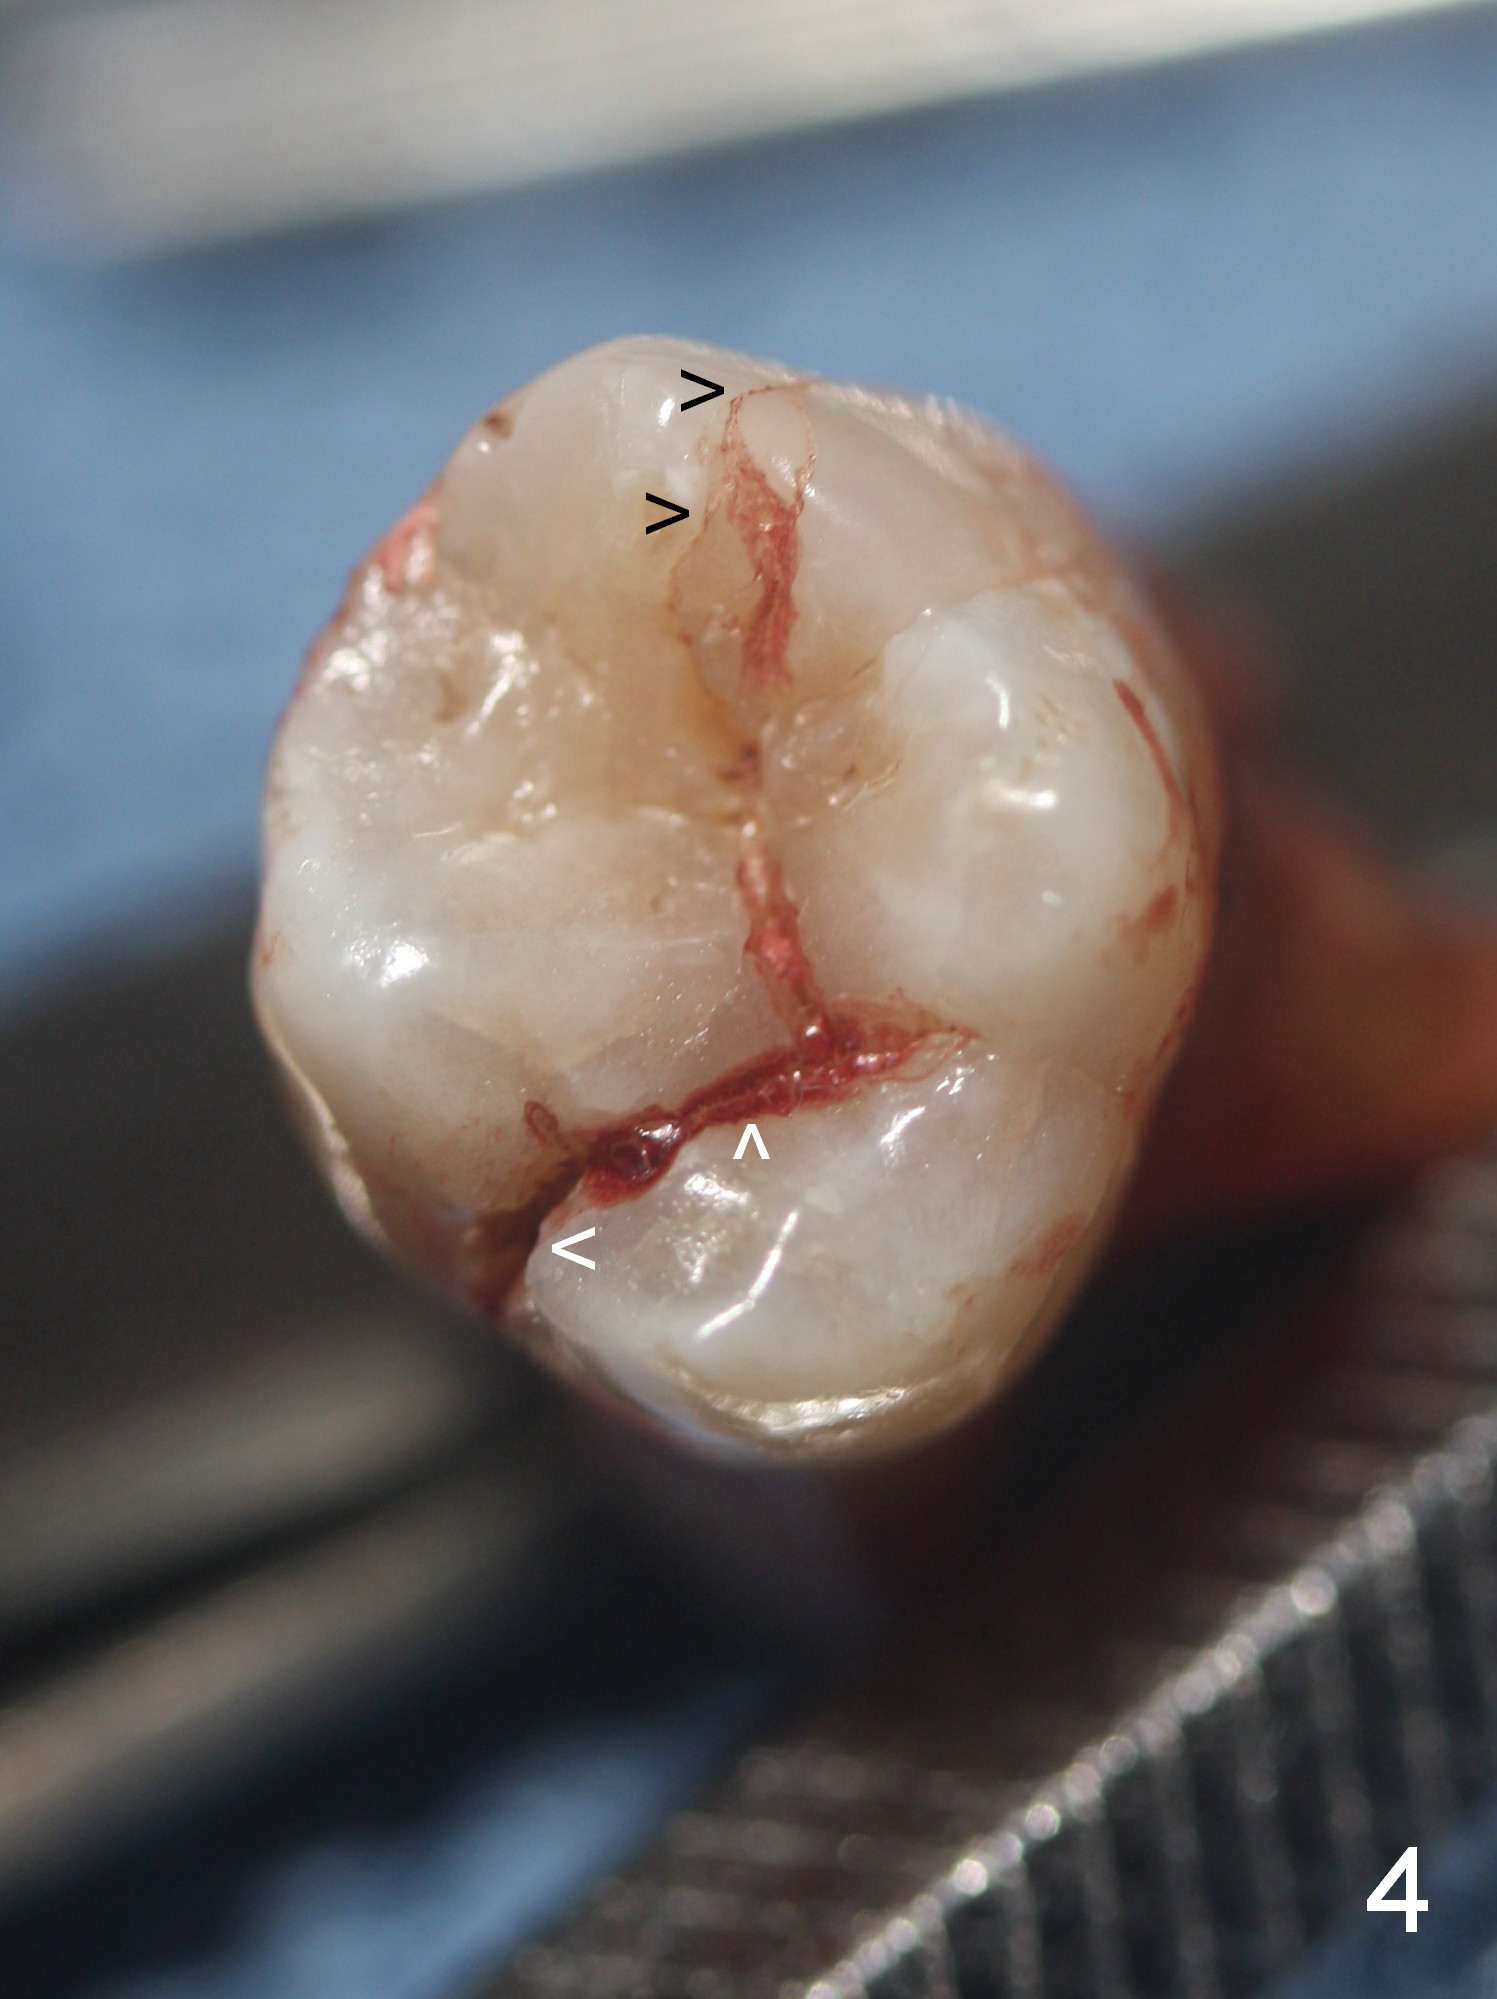

Extensive Crack Line

Approximately 2 months ago, the patient had vague pain in the upper left quadrant. The tooth #15 appeared to have crack tooth syndrome. Recently she developed severe pain and saw a periodontist. When she returns to our office, there is an obvious crack line lingually (Fig.1 <) with a nearby abscess (*). The crack line happens to be visible in X-ray (Fig.2 black <). The buccal abscess is larger (Fig.3 *); more surprising is hardly visible mesiobucal crack line (>).

When the tooth is extracted, the lingual crack line (Fig.4 white <) is contiguous with the mesiobuccal one (black >). The latter corresponds to the white arrowheads in Fig.2. In all the crack line is extensive. The buccal and palatal plates are defective coronally. The large granulation tissue in the furca (Fig.5 *) suggests bone loss in the crestal septum. Most surprising is a crack line in the distal surface of the tooth #13 (Fig.6 ^) and in the mesial surface of #15 (Fig.7). Night guard will be fabricated after an implant crown is cemented at #14.